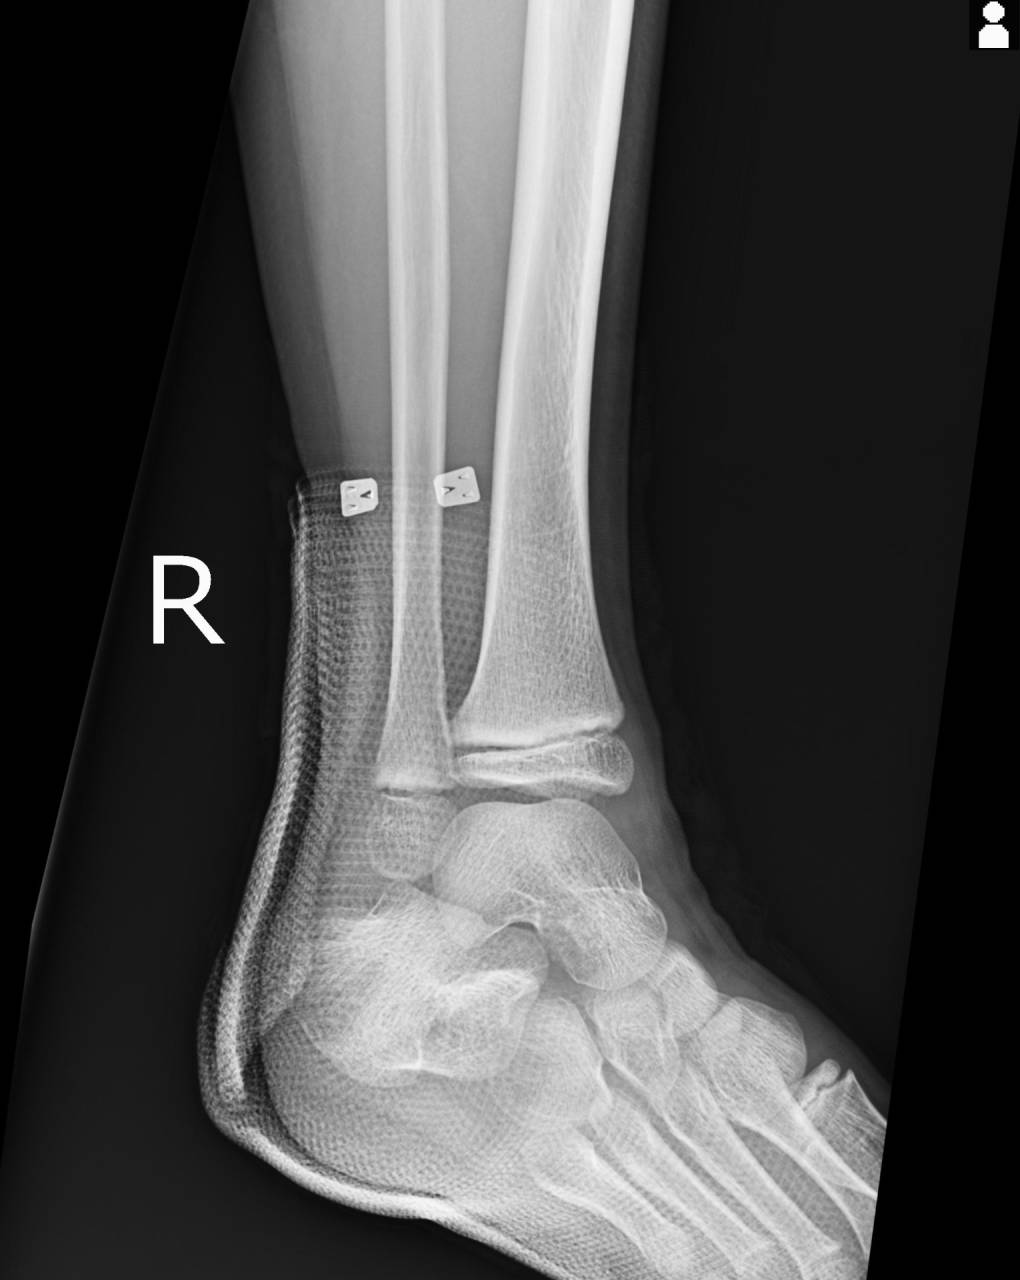

超音波観察装置(エコー)にて組織の状態を確認していくと、腓骨先端の骨端線周囲に骨折の徴候があり、エコー画像での検査で骨折の可能性が濃厚になったため、当整骨院が提携している病院にてレントゲン検査を依頼しました。

撮影した画像を確認すると触診時に疼痛があった部位とエコーにて骨折の疑いがあった部位とレントゲン画像が一致したため、腓骨の先端の骨折として進めていきます。